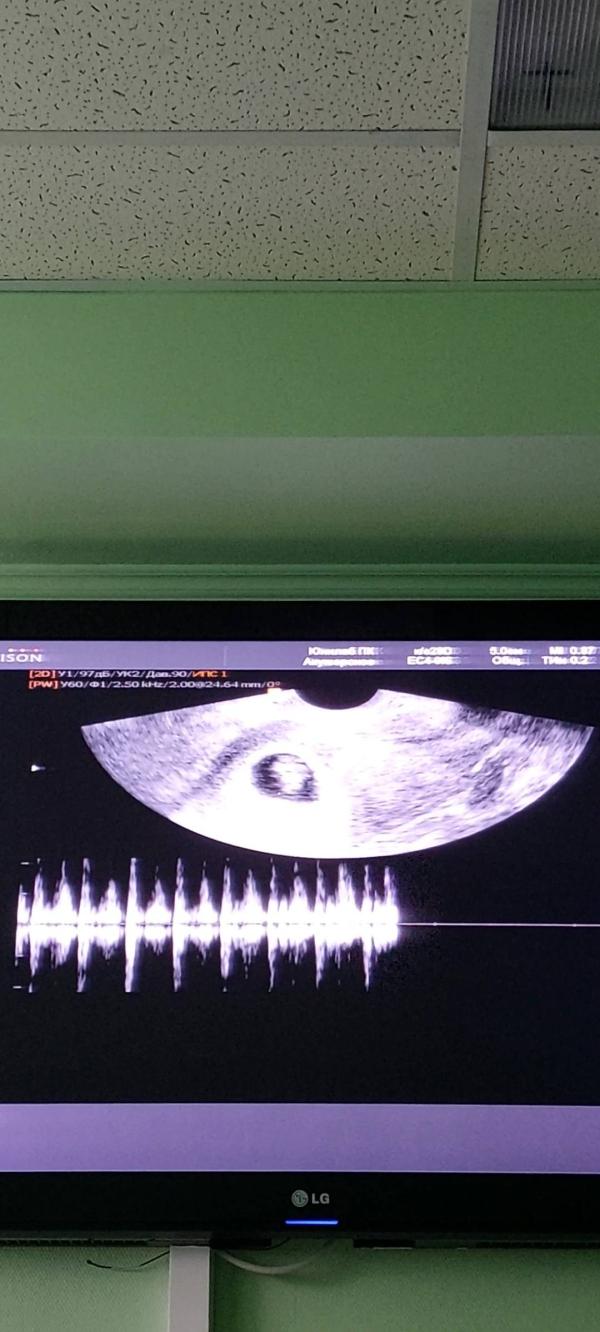

Сегодня было контрольное УЗИ.

Уже смирились, что может быть и 3ня, но малыш один. Я не расстроена, просто приняла это к сведению. Нагрузка на организм матери с 1м малышем все таки меньше, чем с тремя. 2 ПЯ пустые и уже уменьшаются в размерах. В 1м ПЯ маленький малыш с сердечком. Только сейчас начинаю немного осознавать, что беременность наступила. Всё идёт своим чередом. Малыш, расти, будь здоровым и крепким. Мы тебя любим и очень ждём ❣️